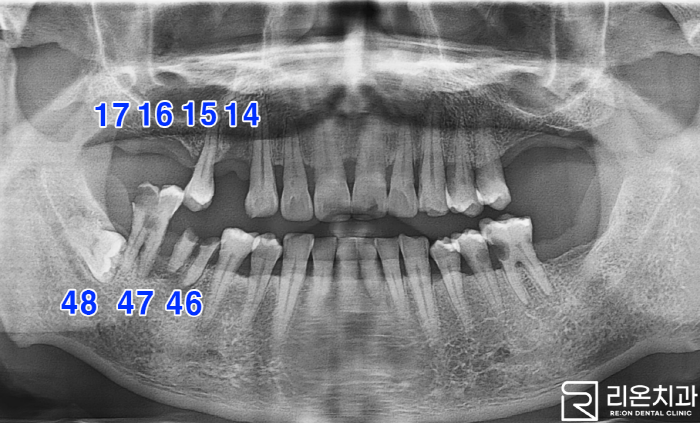

■ 1. 초진

먼저 X-ray 촬영본을 통해 구강 내 어떤 증세가 있는지 확인해 보겠습니다.

2023.01.03

*정준선을 기준으로 환자의 오른쪽에 유독 심한 문제가 나타나고 있습니다. *얼굴을 좌우로 나누는 가상의 선

14, 16, 17번은 *missing *자연치의 결손이나 빠짐

15번은 *mod *mod = 동요도 즉, 치주 질환이나 교합 등

46번에 경우 *root rest *치근 잔존 뿌리만 남아있음. 47번은 *fx(Crown Fracture) *치관 파절

리온 치과 에서 문제가 되는 점을 알아봤는데요 빠른 치료가 필요할 것으로 보입니다.